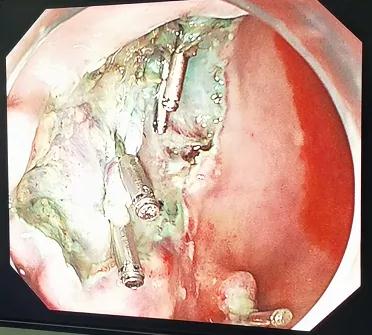

因患者胃“息肉”數(shù)目較多,且其中部分不排除局灶早期癌變可能,在充分評估患者情況基礎(chǔ)上考慮做放大染色胃鏡精查準備。在麻醉科密切配合下,借助高清放大染色胃鏡,我們觀察到幾枚“息肉”相互鄰近,同時發(fā)現(xiàn)了普通白光胃鏡不易察覺的淺隆起病灶,存在可疑早癌征象,與患者家屬充分溝通后,省立醫(yī)院專家指導(dǎo)下,適當(dāng)擴大切除范圍,改行經(jīng)胃鏡胃粘膜下層剝離術(shù)(ESD)。操作非常順利,成功切除了可疑病灶。該病人術(shù)后恢復(fù)良好,正在隨訪中。